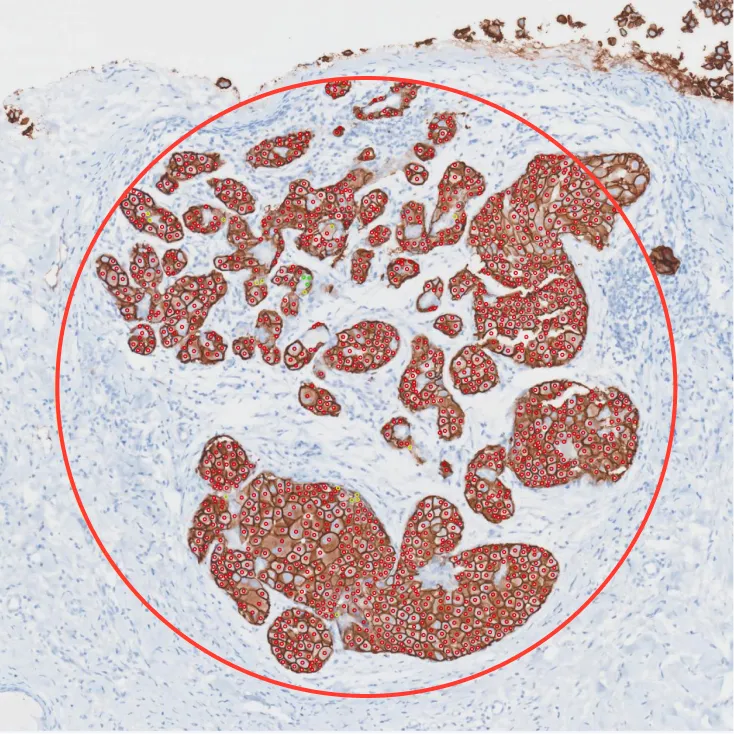

Circle